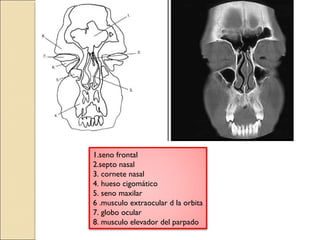

1 .seno frontal

2 .septo nasal

3 .cornete nasal

4. hueso cigomático

5 .seno maxilar

6. musculo extraocular d la orbita

7. globo ocular

8 .musculo elevador del parpado

1.seno frontal

2.septo nasal

3. cornete nasal

5. seno maxilar

6 .musculo extraocular d la orbita

8. musculo elevador del parpado